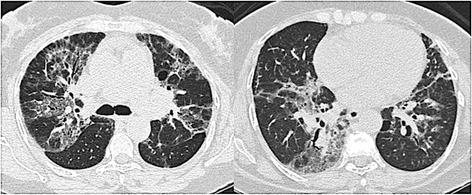

There were 68 cases of ACIF, most of them women. The mean age was 57 ± 12 yr. Dyspnea, cough, restrictive pattern at spirometry and oxygen desaturation at exercise were common. A reticular pattern with peribronchovascular infiltrates was found in 79% of the cases. The etiologies of ACIF were hypersensitivity pneumonitis in 29 (42.6%), gastroesophageal reflux disease in 17 (25.0%), collagen vascular disease in 4 (5.9%), a combination of them in 15 cases and idiopathic in 3 (4.4%). The median survival was 116 months (95% CI = 58.5 - 173.5). Lower values of oxygen saturation at rest, presence of cough and some histological findings--organizing tissue in the airways, fibroblastic foci and microscopic honeycombing--were predictors of worse survival.

共有68例ACIF患者,其中大多数为女性。平均年龄为57±12岁。呼吸困难、咳嗽、肺活量测定时的限制性模式和运动时的氧饱和度下降很常见。79%的病例发现有支气管血管周围浸润的网状模式。ACIF的病因包括29例(42.6%)过敏性肺炎、17例(25.0%)胃食管反流病、4例(5.9%)胶原血管病、15例为它们的组合以及3例(4.4%)特发性。中位生存期为116个月(95%CI = 58.5 - 173.5)。静息时较低的氧饱和度、咳嗽的存在以及一些组织学表现——气道内的机化组织、成纤维细胞灶和显微镜下的蜂窝状改变——是生存较差的预测因素。